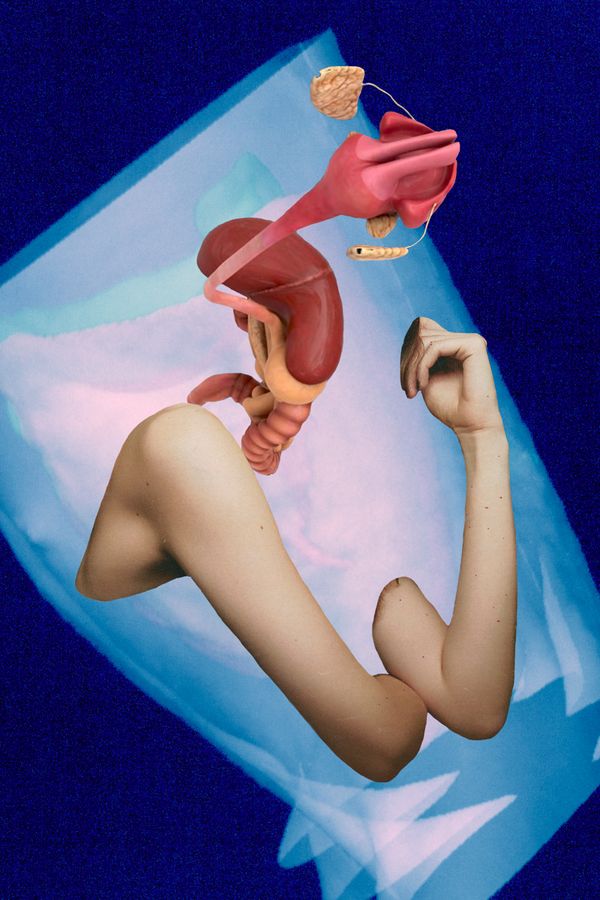

Due to health problems within my family including myself this work derives from a long- term engagement with the human body, its mal-functions and collateral mental issues.

Due to health problems within my family including myself this work derives from a long- term engagement with the human body, its mal-functions and collateral mental issues.

Since the topic being serious and threatening at times, the analysis within the terms of art began to shift from depressing states and strong depictions to more symbolic style of expression alleviating the whole issue.

Combining digital 3-D models of inner organs from the web with scanned cut-outs from magazines, different kind of free associations are made possible. The background consisting of CTs from my check-up enhances the issue of the fragility of our body.

Each image describes a mental state during this period of endurance.